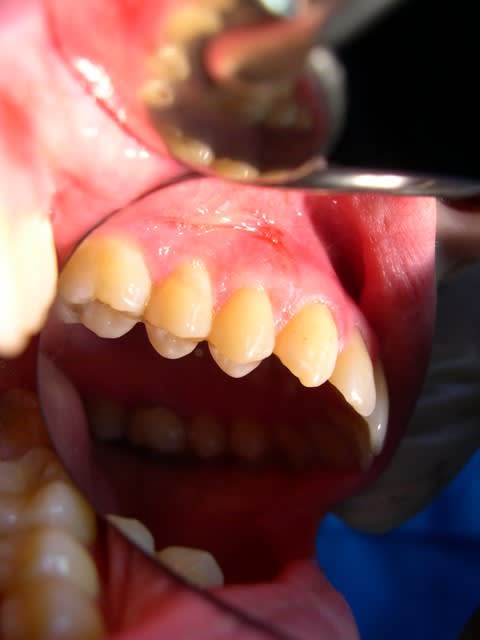

voilà un cas clinique où j'ai dû enlever un fil résorbable resté en place 2 mois, avec une jolie inflammation.

c'est ma faute, j'l'avions point vu.

eh oui, je l'ai enlevé hier. on voit le saignement sur la dernière photo. il a fallu le chercher, mais il est sorti intact!